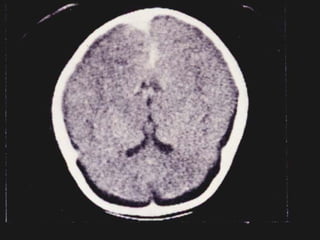

MENINGITIS BACTERIANA Diagnostico: Otros estudios de utilidad: Tomografía axial computarizada. Resonancia magnética.

MENINGITIS BACTERIANA Diagnostico:Otros estudios de utilidad: Tomografía axial computarizada. Resonancia magnética.